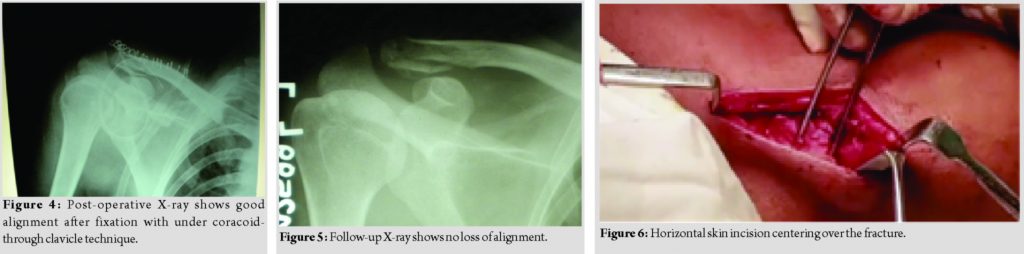

A 40-year-old patient presented to our facility, with a history of fall on the shoulder. After clinical and radiological examination, he was diagnosed with a distal clavicle Neer type 2B fracture (Fig. 1). The patient was operated within 1 week of the injury.

The patient was positioned supine on the operating table. A 5–6cm horizontal skin incision was utilized to expose the clavicle (Fig. 2). The deltoid-trapezoidal fascia was incised in line with the anterior border of the clavicle. The deltoid was divided along its fibers till the base of the coracoid was accessed. All the soft tissues from the superior surface of the clavicle were removed to gain access to the superior and inferior surface and to the distal and proximal fracture segments. The soft tissues were cleared from the medial and lateral end of the coracoid “knee” to enable passage of the sutures underneath the coracoid. A Mixter or a Satinsky clamp can beutilized to pass a Mersilene tape and Ethibond number 5 sutures below the coracoid from medial to the lateral side and near its “knee”(Fig. 3 and 4). Two holes, one each in the medial and lateral fragment, were drilled in the superior-inferior direction, 1–2 cm from the fracture site with the help of 3.2 mm drill bit (Fig. 5). One suture limb each of the Ethibond and the Mersilene tape was passed through the hole in the medial fragment in the inferior-superior direction (Fig. 6) and then passed through the second hole in the lateral fragment to exit inferiorly. The medial clavicle was reduced to the lateral end by a downward vertical pressure. First, the Ethibond was tied as it has good knotting properties and then the Mersilene tape was tied to give additional mechanical support. Since the knots were tied below the clavicle, there was no knot prominence or skin irritation. The deltoid-trapezius fascia and the skin are closed over the whole construct. Post-operative X-rays showed good reduction and opposition of the fracture (Fig. 7). Follow-up X-rays at 3 months showed good alignment with no loss of reduction (Fig. 8).